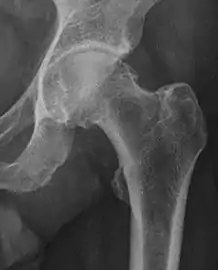

Projectional radiography ("X-ray")is often considered first line for FAI.[10] Anterior-posterior pelvis and a lateral image of the hip in question should be attained.[10] A 45-degree Dunn view is also recommended.[10][19]

Femoral head-neck offset | ![]() |

Offset of the femoral head with regard to most prominent aspect of the femora neck | >10 mm |

Offset percentage | Femoral head-neck offset related to femoral head diameter | >0.18

| |